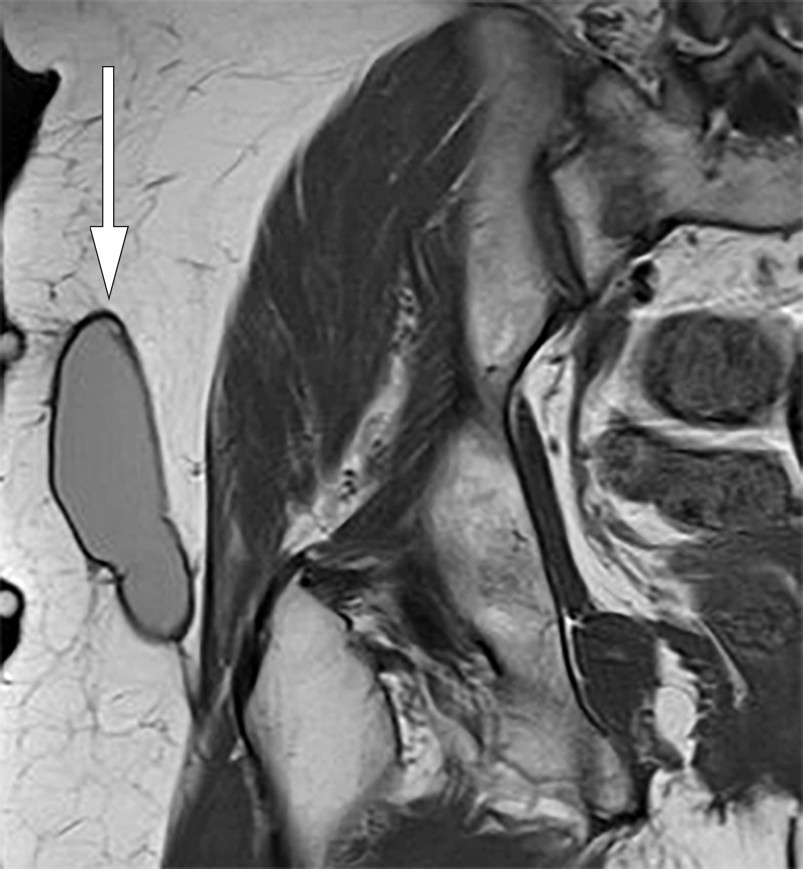

Ved fireukerskontroll var det intet residiv. Pasienten kjente bare et lett ubehag i området, og hun kunne slutte med kompresjonsbehandling. Ved tolvukerskontroll viste MR av høyre hofte tilnærmet full regress av lesjonen (figur 2). Ved ettårskontroll var pasienten residivfri klinisk og radiologisk. Hun hadde sekvele i form av lett inndragning av huden.